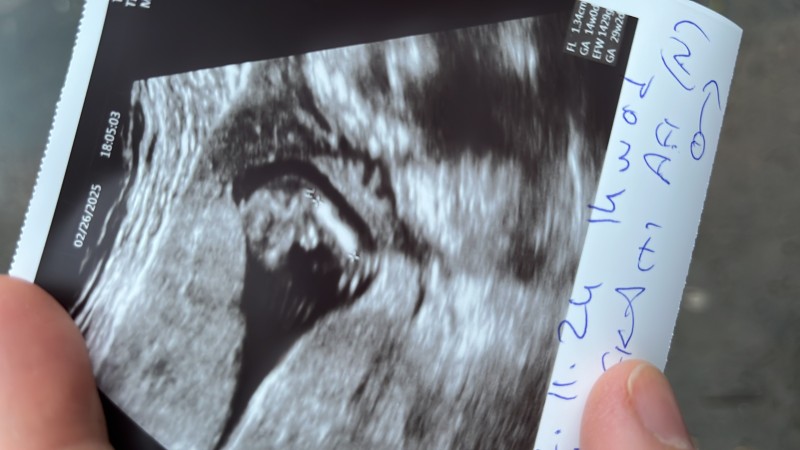

Kızlar erkek mi bebeğim

image

Bacak arası açmamış sanki tam

Bilmiyorum ki cnm baya pipi gibi bu 🥲

Bacak arası dolu canım Rabb'im gönlüne göre versin inşallah bı kızın olur ve iki meyveyi de tatmış olursun.

Erkek canım görünüyor zaten

Herkes bacak arasında bir şey görmüş ben göremedim kızım da arası boştu görünse görünür kapalı da olsa bacaklarinin üstünde🤭

Orda uzun bişey var gibi doktor sadece çıkıntı var erkek gibi diyor gerisi yok

Ben bacak arasında birşey görmedim ama dilerim sağlıklı hayırlı bir kız evlatir. Kız evlatta çok güzel bir nimet erkek evlat gibi :)

Bacak arasındaki pipi olsa doktor da derdi bence net olsaydı ama oğlumun ultrason benziyor erkek gibi

Sadece çıkıntı var diyor başka bişey demiyor